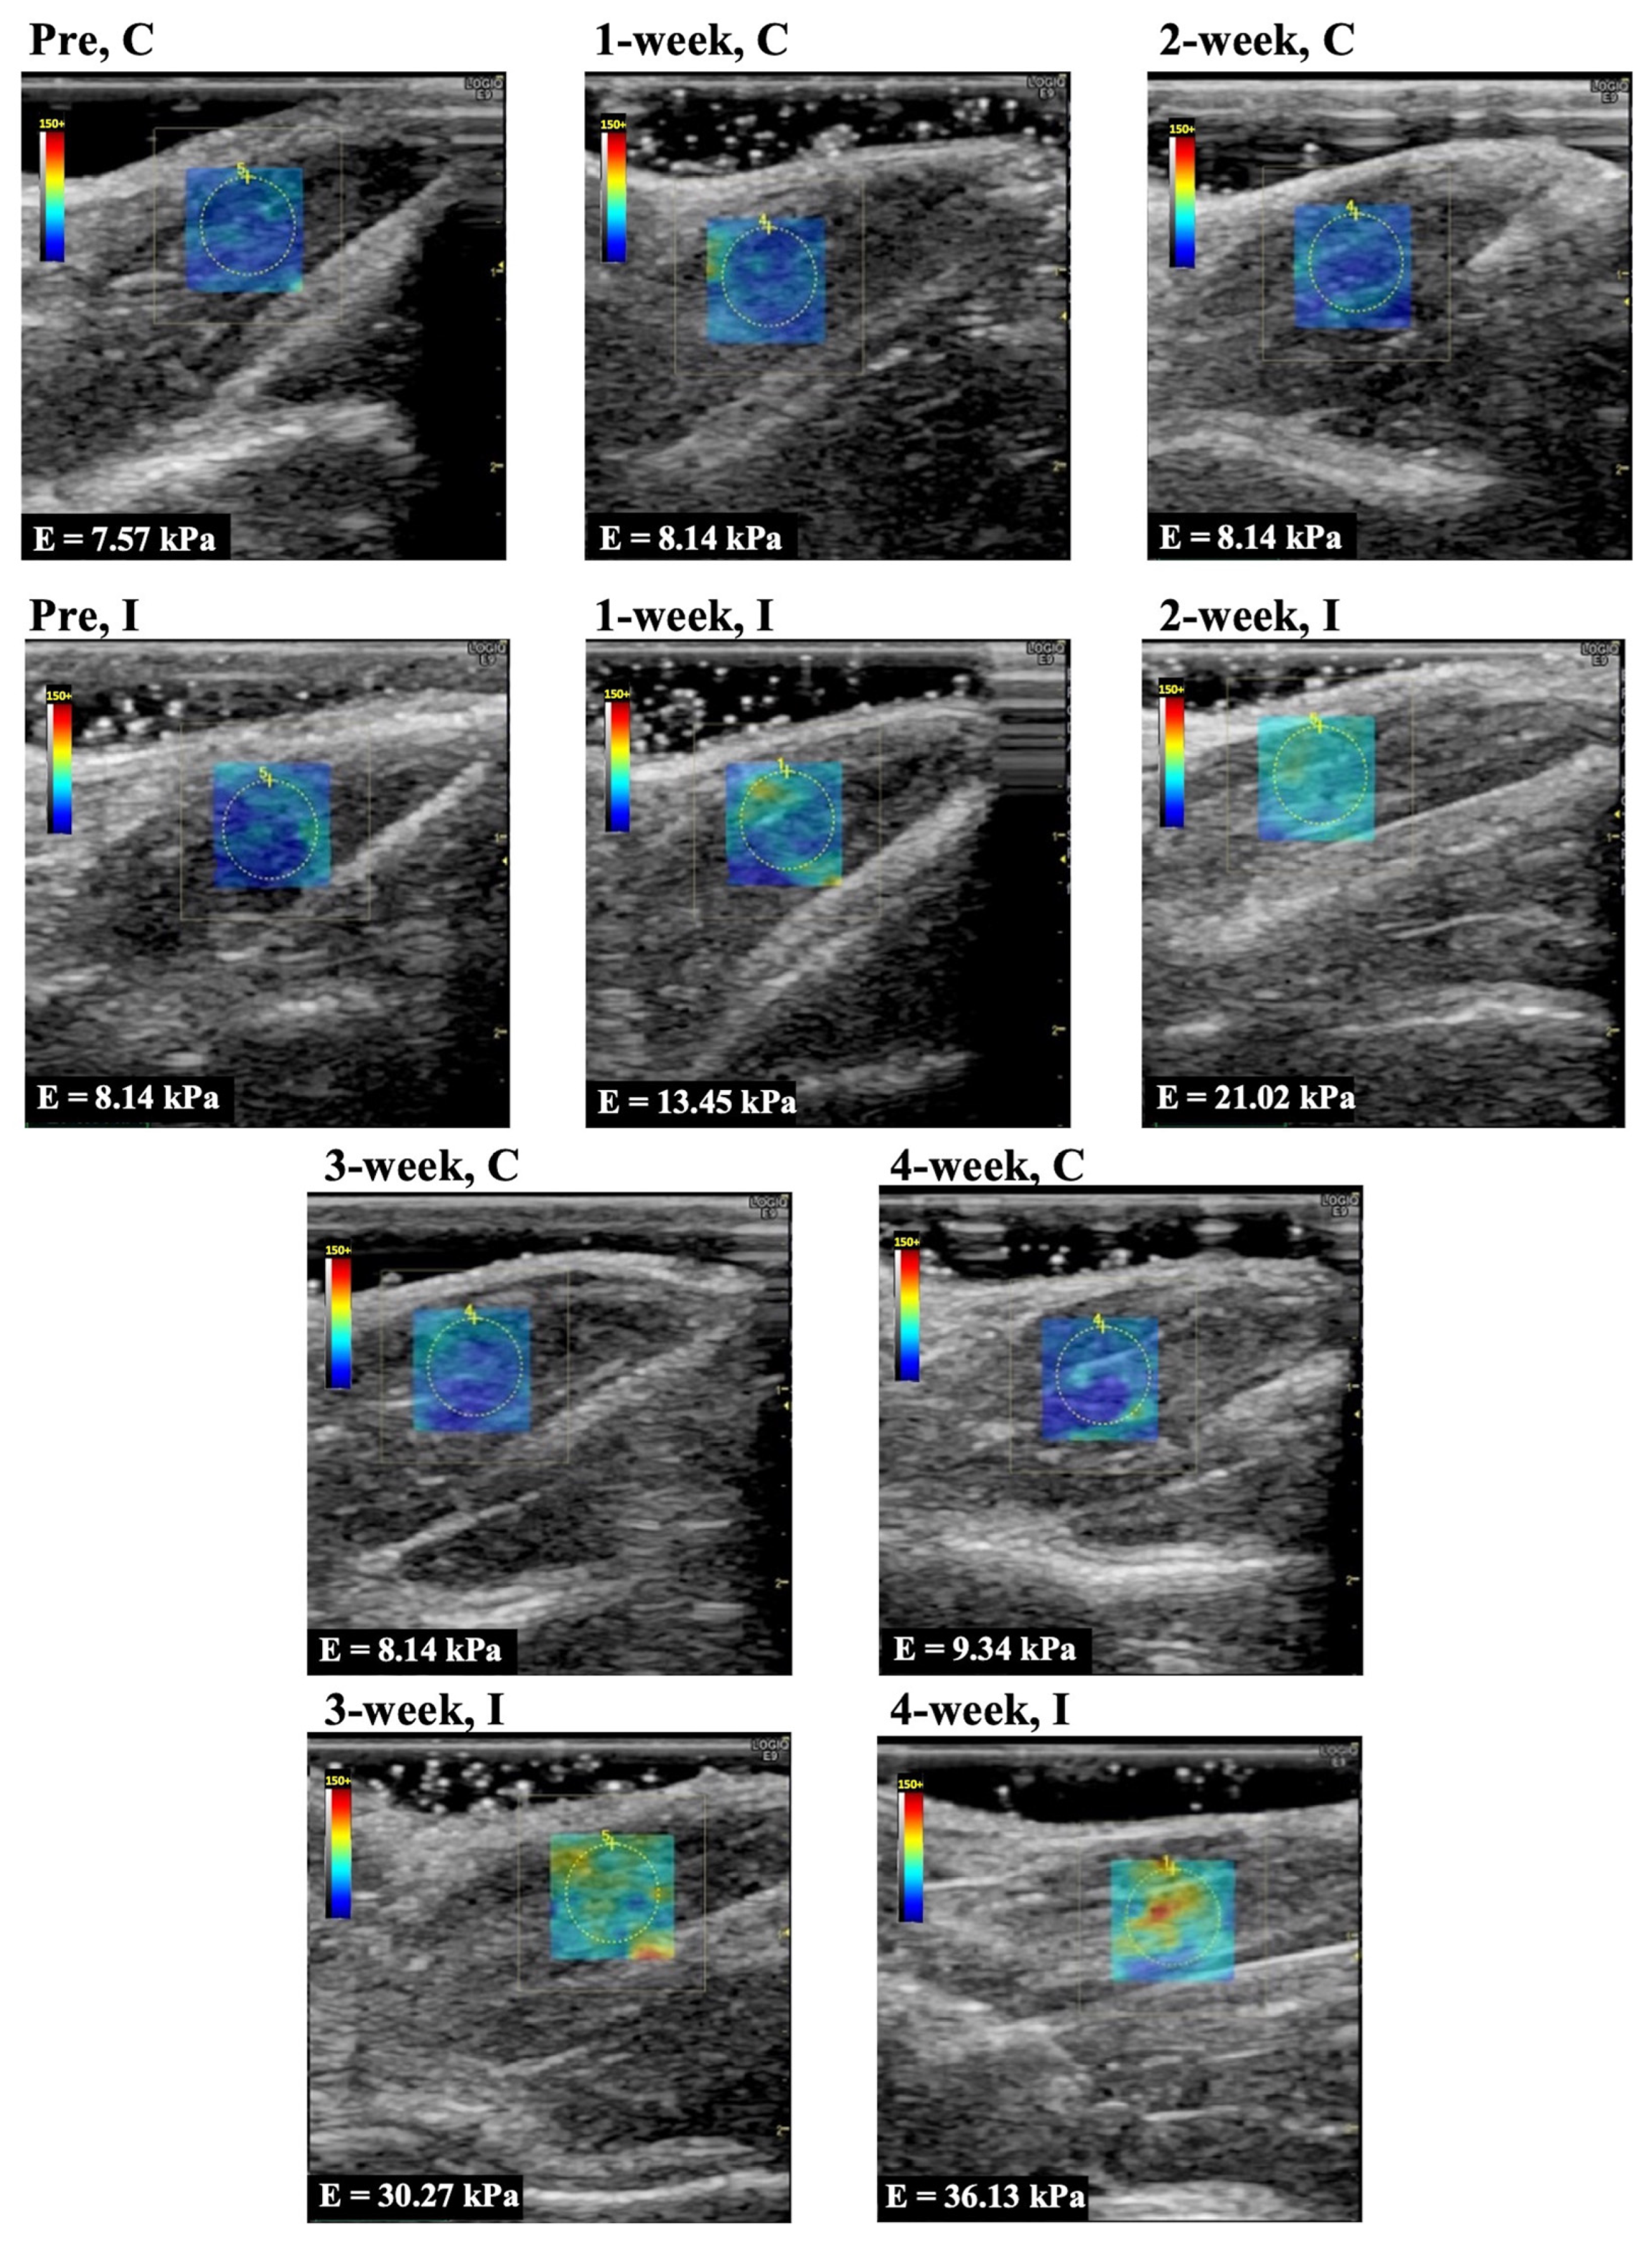

Representative longitudinal ultrasound shear wave elastography images of the rectus femoris, vastus lateralis, and vastus medialis muscle are shown in Figure 2, Figure 3, and Figure 4, respectively. In Group I, cyan, orange, and red colors increased during the immobilization period, suggesting an increased elastic modulus.

The elastic modulus of the rectus femoris, vastus lateralis, and vastus medialis muscle as determined by ultrasound shear wave elastography are shown in Figure 5A–C. The elastic modulus of the rectus femoris, vastus lateralis, and vastus medialis muscles in Group C were 8.6 ± 1.0, 7.4 ± 1.3, 7.6 ± 1.1 kPa (mean and standard deviation) in before experiment, 7.5 ± 1.4, 7.8 ± 0.8, 8.7 ± 0.5 kPa in 1 week, 7.4 ± 1.2, 7.1 ± 1.6, 8.0 ± 1.5 kPa in 2 weeks, 8.6 ± 1.2, 7.5 ± 0.9, 8.4 ± 0.7 kPa in 3 weeks, and 8.0 ± 1.0, 7.4 ± 1.0, 8.5 ± 0.7 kPa in 4 weeks, respectively. The elastic modulus of those muscles in Group I was 8.3 ± 1.2, 7.4 ± 1.1, 7.7 ± 1.1 kPa in the before experiment, 15.0 ± 1.4, 15.2 ± 2.2, 14.5 ± 1.5 kPa in 1 week, 20.1 ± 1.7, 19.6 ± 2.2, 18.9 ± 2.5 kPa in 2 weeks, 29.0 ± 2.1, 28.8 ± 1.7, 29.2 ± 2.4 kPa in 3 weeks, and 30.6 ± 2.7, 32.9 ± 4.0, 33.1 ± 3.4 kPa in 4 weeks, respectively. The elastic modulus for all periods in Group I was significantly higher (p = 0.0001 in all muscles) compared with the same periods in Group C. In Group I, the elastic modulus increased after more than 3 weeks of immobilization compared to the 1 and 2 week immobilizations.

Figure 2. Representative shear wave elastography of the rectus femoris muscle. C, control group; I, immobilization group; Pre, before the experiment; E, elastic modulus. The rectangle indicates the region of interest. The measurement circle was 5 mm in diameter.